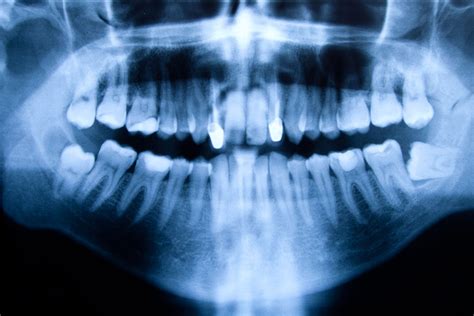

- Revisión y diagnóstico profesional: Agenda una visita con tu dentista para que evalúe el bulto. El odontólogo examinará la lesión; muchas veces con solo verla y palparla puede identificar de qué se trata. En otros casos solicitará radiografías (por ejemplo, una ortopantomografía) para ver quistes dentro del hueso o asociados a raíces dentales que no son visibles externamente.